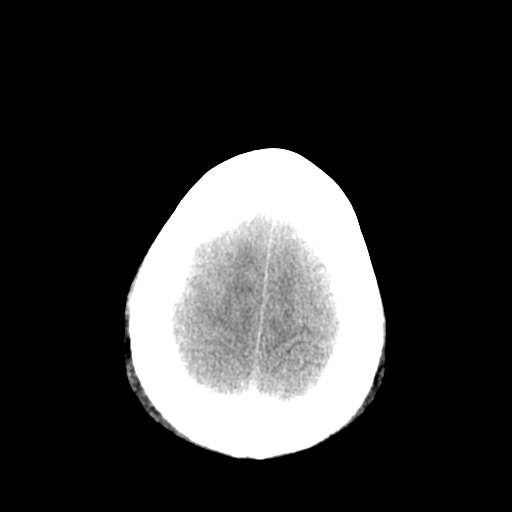

以下是引用李衡钧在2008-9-18 17:37:00的发言:[br]脑质内见两个低密度灶,其内见点状高密度。[br]考虑脑囊虫。建议增强或进一步检查确诊。

以下是引用chmh在2008-9-18 18:45:00的发言:[br]考虑脑囊虫病可能性大,建议行ct增强检查及血清和脑脊液囊虫补体结合试验.